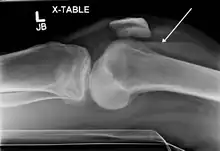

X-ray of Hemarthrosis